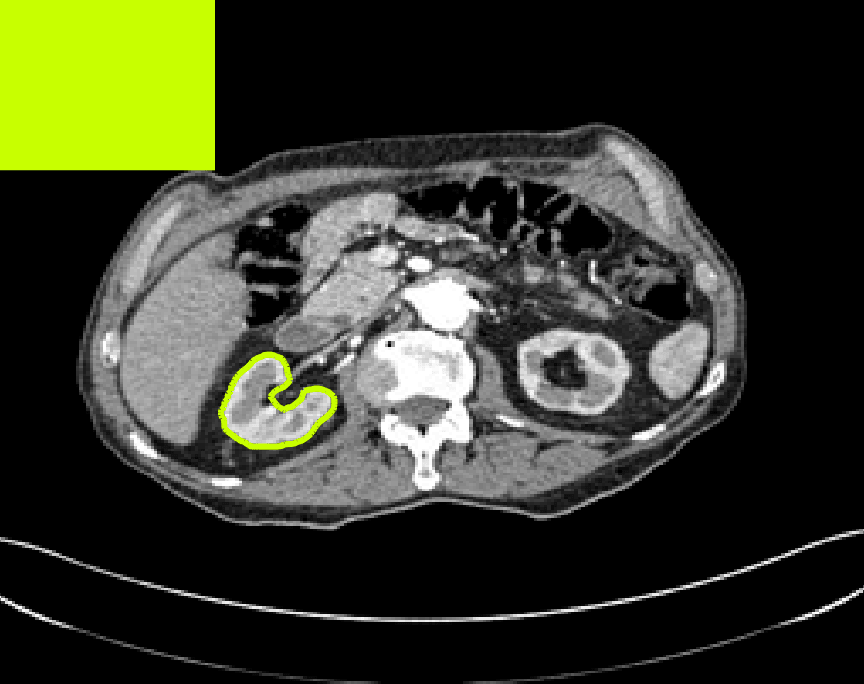

Test Images. We will perform initial tests on the images shown in Figs. 5–7. We have provided the ground truth and initialisation used for each image. Test Images 1–3 are synthetic, Test Image 4 is an MRI scan of a knee, Test Images 5–6 are abdominal CT scans, and Test Images 7–9 are lung CT scans. They have been selected to present challenges relevant to the discussion in §2. We focus on medical images as this is the application of most interest to our work. In the following we will discuss the results in terms of synthetic images (1–3) and real images (4–9). We also test the proposed approach on a larger data set of 30 CT images (a sample of which is presented in Fig. 18), comparing against existing selective methods detailed in §3.

In order to further establish the robustness of our method, we now introduce the results of testing our approach against competing interactive segmentation methods on a larger data set. The results are presented in Fig. 17, showing a boxplot of accuracy in terms of TC on a set of 30 CT images (excluding outliers). The target structure we consider is the spleen, as this consists of a relatively homogeneous foreground, appropriate for the approach considered. The data has been manually contoured providing ground truth data for the image set. We compare CAC Nguyen:12 and SRW SRW against our method with five variations of user input for each image. It is worth emphasising here that the input used in the tests is identical for each approach and was not refined in any way. It was designed to mimic what a user, unfamiliar with each approach, might select intuitively. A representative example for three images is shown in Fig. 18. This shows foreground (red) and background (blue) user input regions. For our method, we define the red region as as discussed in §1 and enforce hard constraints on the blue region. We refer to the results of the proposed approach using this input as Ours (i). We also include results of randomising the user input in an identical way to §7.3. For each image we generate 1000 simulated user input choices, which we present as Ours (ii). It is important to note that the difference between Ours (i) and (ii) is only the definition of . The method and parameters are fixed between each.